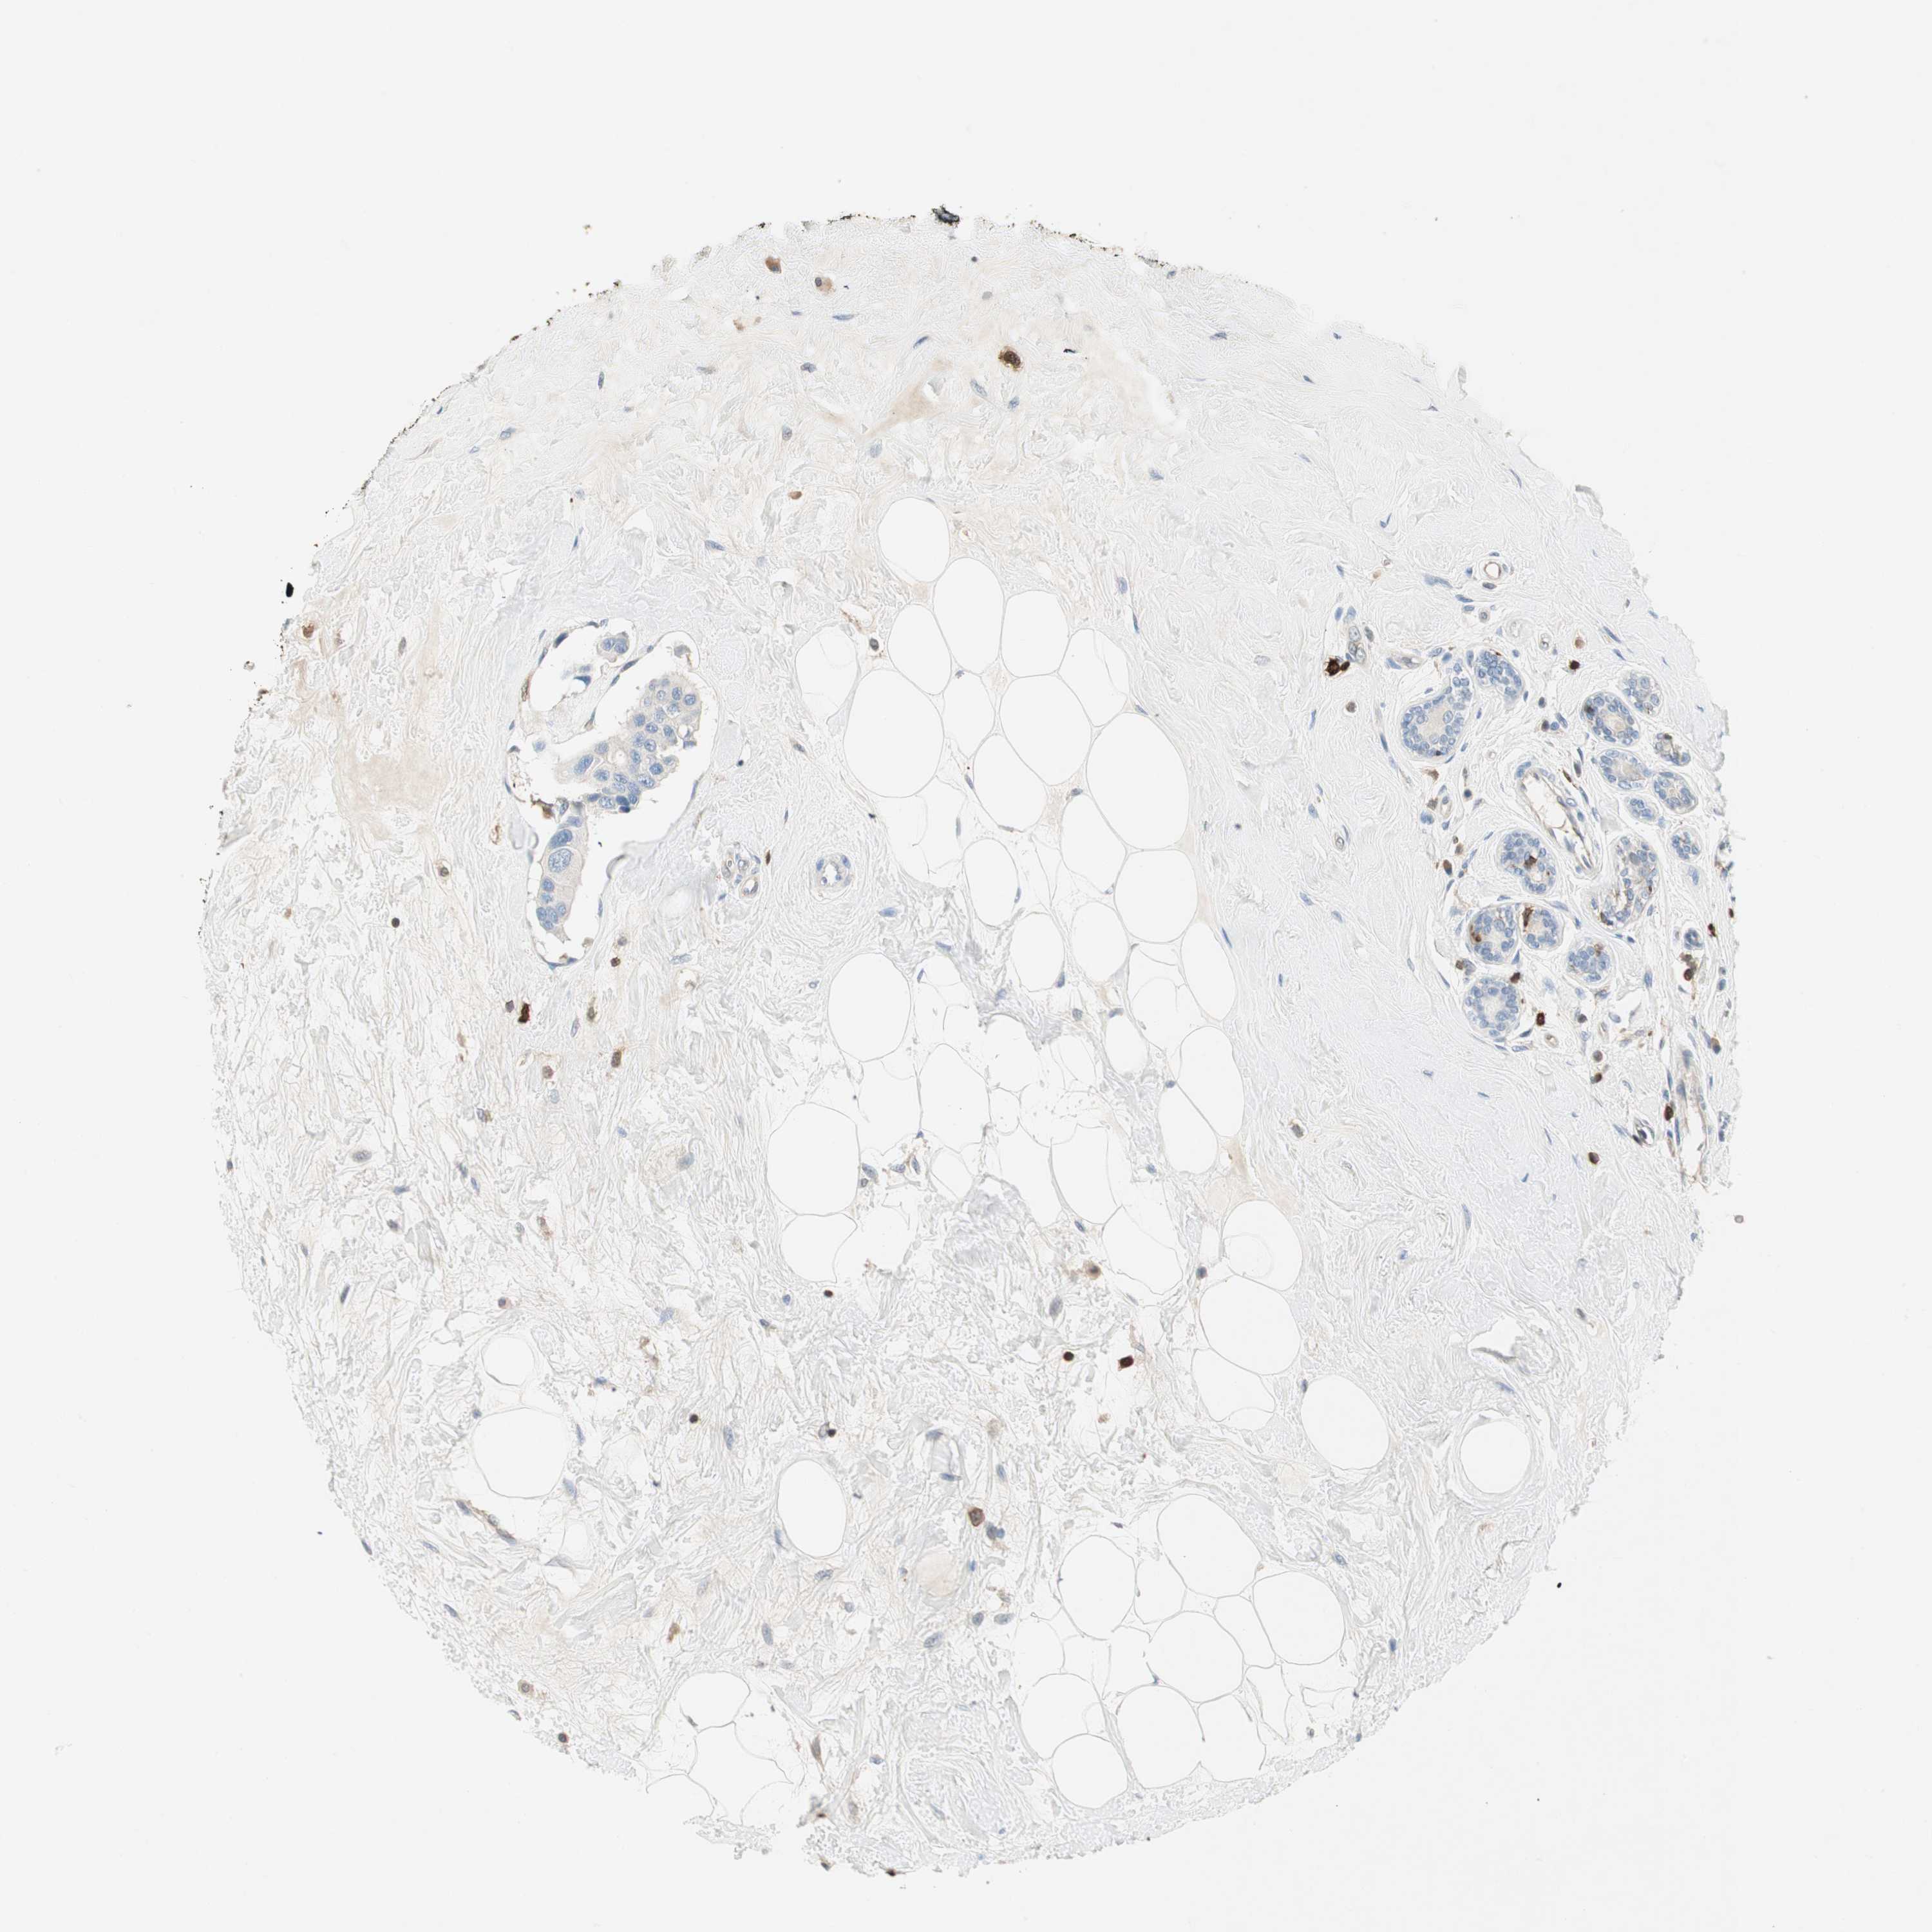

BRCA TCGA BRCA VALIDATION PROTEIN EXPRESSION